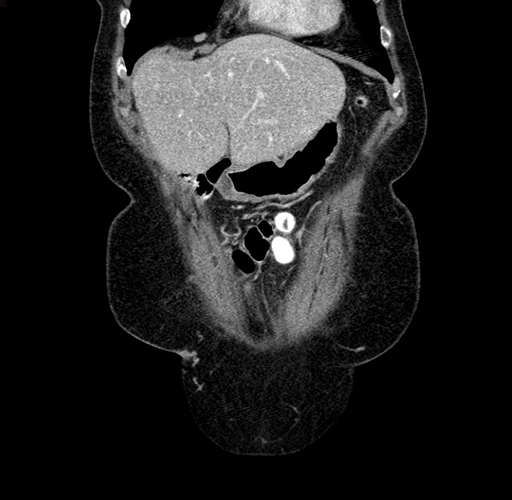

Pre-Chemo: Axial Venous

Pre-Chemo: Coronal Venous